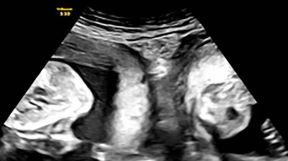

Žena s dvije maternice rodila blizance: Postoji 6 tipova anomalije maternice, koji su simptomi neobičnog položaja?